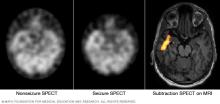

SPECT scan

These SPECT images show the blood flow in the brain when there's no seizure activity (left) and during a seizure (middle). The subtraction SPECT coregistered to MRI (right) helps pinpoint the area of seizure activity by overlapping the SPECT results with brain MRI results.

• Single-photon emission computerized tomography, also called SPECT. A SPECT test uses a small amount of low-dose radioactive tracer. A healthcare professional puts the tracer into a vein. This makes a detailed, 3D map of the blood flow in the brain during a seizure. A form of a SPECT test called subtraction ictal SPECT coregistered with magnetic resonance imaging, also called SISCOM, may give even more-detailed results.